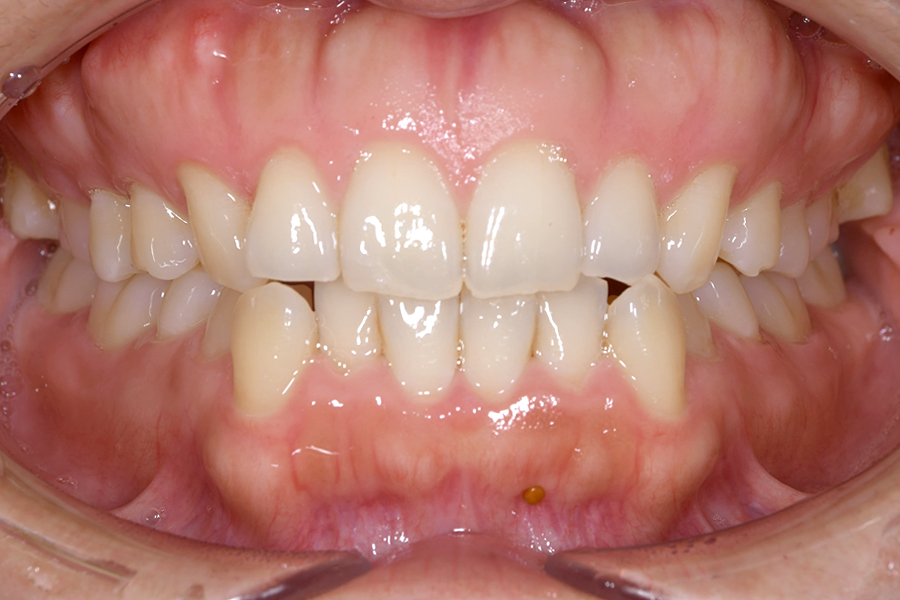

| 主訴 | 見た目を治したい、歯を白くしたい |

|---|---|

| 治療期間 | 1年6か月 |

| 治療費 | マウスピース矯正と ホームホワイトニングセット 1,022,350円(税込) |

| 治療内容 | 目立ちにくいマウスピース矯正 (非抜歯矯正) 歯と歯の間に隙間をつくることにより、歯列弓を広げながら治療を行いました。 また矯正用マウスピースをトレー代わりにし、ジェルを入れてホームホワイトニングを同時に行っております。 |

| 治療のリスク | ・後戻りする可能性があるのでリテーナーを最低でも矯正期間以上はつける必要があります。 ・ホワイトニング後、一時的に痛みが出る場合があります。 |